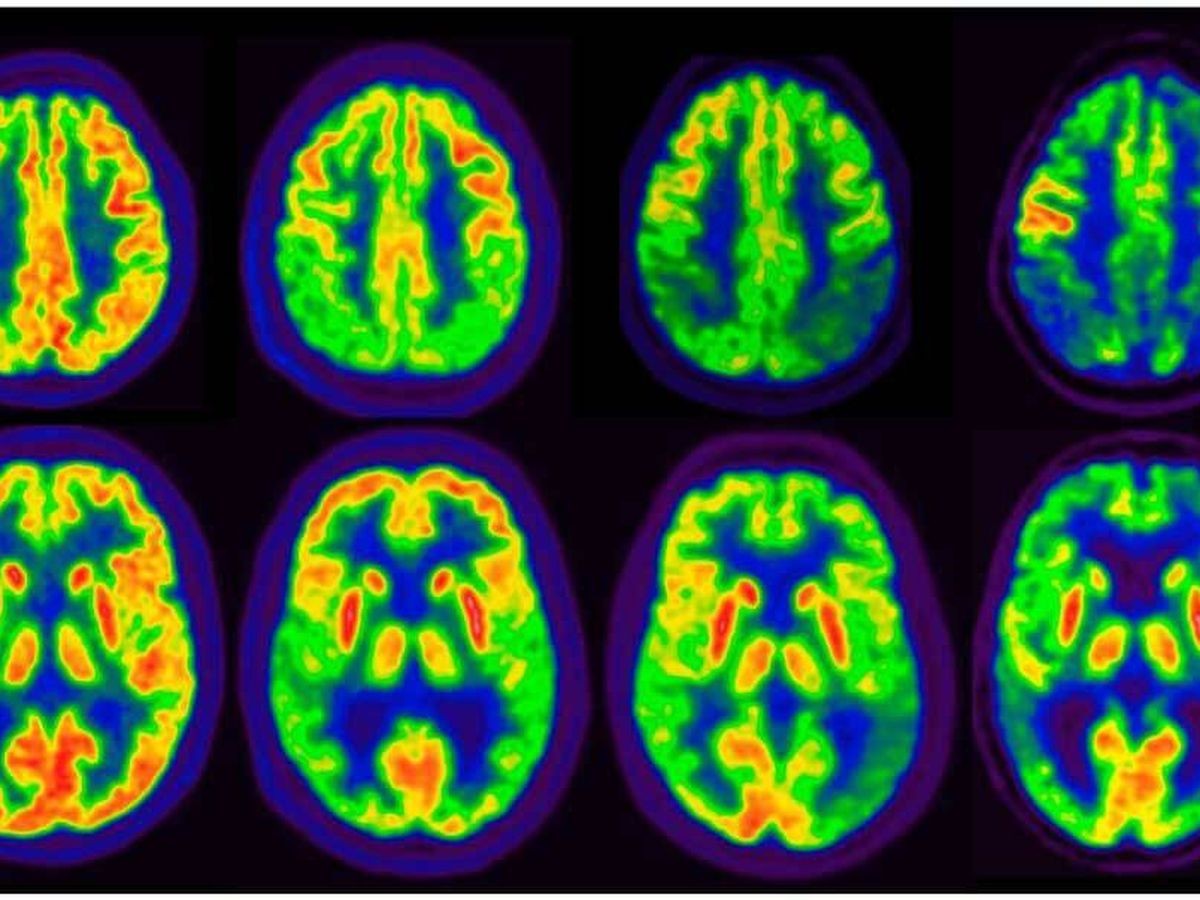

Cientificos confirman que el fármaco contra el Alzheimer lecanemab ralentiza un 27% el deterioro cognitivo. El descubrimiento se da luego de administrarlo durante 18 meses, según un estudio de fase 3 presentado este martes en la 15 Conferencia sobre Ensayos Clínicos de la Enfermedad de Alzheimer (CTAD, por sus siglas en inglés) y publicado en la revista científica ‘The New England Journal of Medicine’, una de las más prestigiosas a nivel mundial.

Sin embargo, los resultados, publicados en la revista especializada New England Journal of Medicine, apuntaron también efectos secundarios, a veces graves. En total, 17,3% de los pacientes que recibieron lecanemab sufrieron hemorragias cerebrales, frente a 9% de los pacientes del grupo placebo.

Un 12,6% de los pacientes tratados con lecanemab sufrieron edemas cerebrales contra solo 1,7% en el grupo placebo.